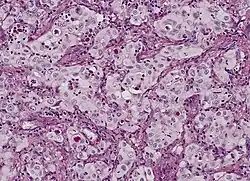

Adenokarzinom mit Schleimbildung

Bis zu 20 Prozent der Lungenkarzinome sind Adenokarzinome. Sie entstehen aus schleimproduzierenden Zellen und entwickeln sich bevorzugt in Narbengewebe (z. B. alter Tuberkulose). Der Tumor liegt meist in der peripheren Lunge. Auch hier ist eine frühe Metastasierung typisch, die sowohl über die Lymphbahnen als auch über die Blutbahn erfolgt, und zwar bevorzugt in das Gehirn, die Leber und die Nebennierenrinde. Histologisch sieht man vor allem Drüsenformationen. Eine besondere Rolle spielt das vergleichsweise seltene bronchioloalveoläre Karzinom. Diese Sonderform, die ungefähr ein bis neun Prozent der untersuchten Bronchialkarzinome ausmacht, wächst langsam und innerhalb der anatomischen Strukturen. Radiologisch wird sie deshalb häufig mit einer Pneumonie verwechselt. Im Gegensatz zu anderen Bronchialkarzinomen besteht anscheinend kein ursächlicher Zusammenhang zu inhalativen Noxen.

Histologisch sollten je nach Subtyp drüsige, papilläre oder auch solide atypische epitheliale Strukturen mit Zeichen einer Schleimbildung zu sehen sein. Immunhistochemisch sind Adenokarzinome meist positiv für CK7 und negativ für Plattenepithelmarker wie CK5/6 und p63. Die Wachstumsrate (Ki-67) ist deutlich erhöht, aber nicht so stark wie beim SCLC. Der Nachweis von TTF1 spricht für ein in der Lunge entstandenes Adenokarzinom (DD Metastase eines Schilddrüsenkarzinoms). Bei Verdacht auf Vorliegen einer Metastase oder eines die Lunge infiltrierenden malignen Pleuramesothelioms können weitere Marker zum Einsatz kommen, um die Lokalisation des Primärtumors näher einzugrenzen.